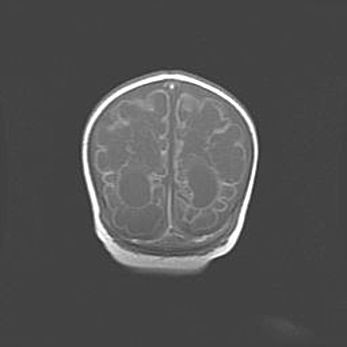

Открытая гидроцефалия.

Возраст: 9 месяцев 12 дней

Вес: 6800 г

Пол: мужской

Окружность головы: 41,5 см

Срок гестации: 28 недель

Гидроцефалия головного мозга у новорожденных имеет характерный признак: опережающий рост окружности головы приводит к визуально хорошо определяемой гидроцефальной форме сильно увеличенного в объёме черепа. Детские неврологи определяют следующие симптомы гидроцефалии у грудничков: выбухающий напряжённый родничок, частое запрокидывание головы, смещение глазных яблок к низу.